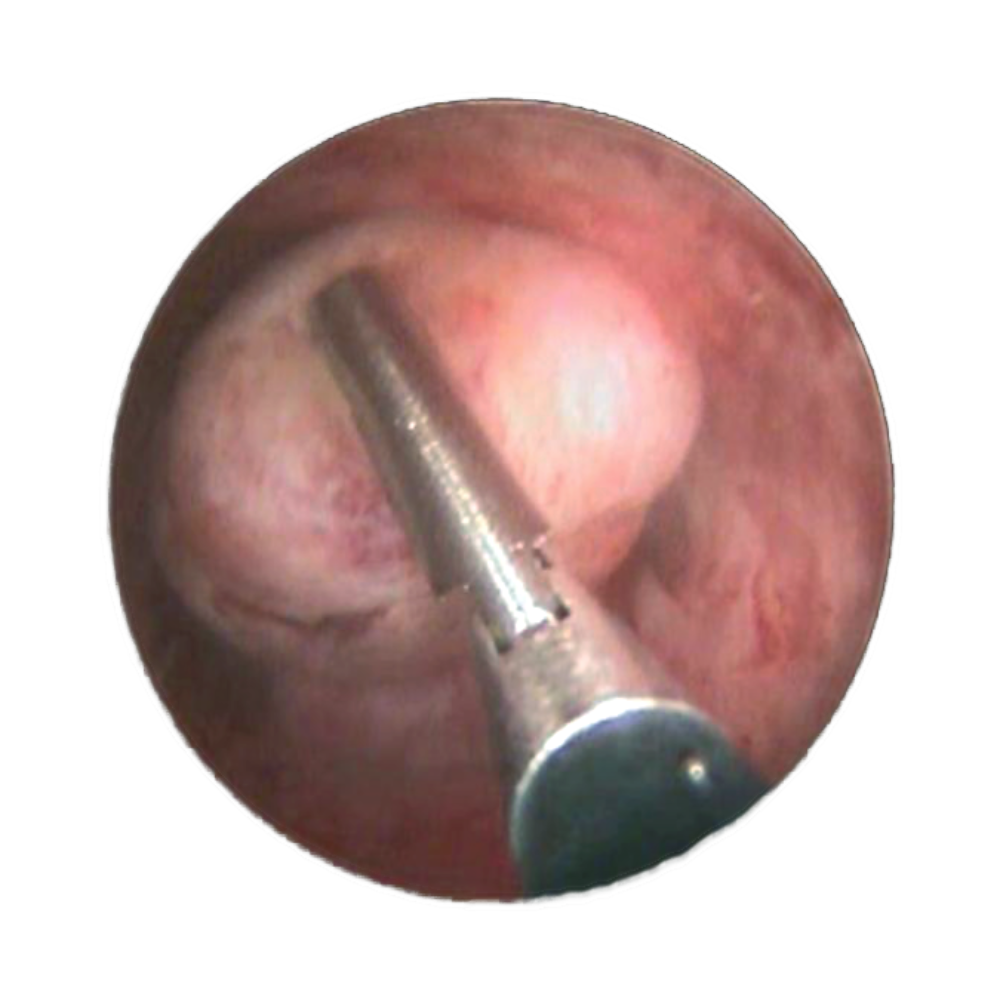

MaxiCare

La résection bipolaire en 9mm